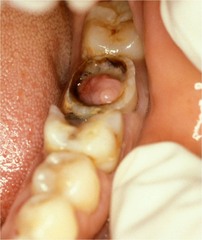

chronic hyperplastic pulpitis

-Red or pink nodule protruding from the pulp chamber or a tooth with a large open carious lesion (usually molars)